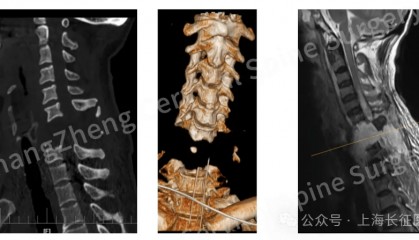

全球罕见!中国医生救回“身首离断”患者 从业近30年,上海长征医院颈椎外科病区主任陈华江教授接诊过无数凶险的颈椎外伤患者,但称得上是“身首离... 抹茶交易平台app 2025-08-18 25